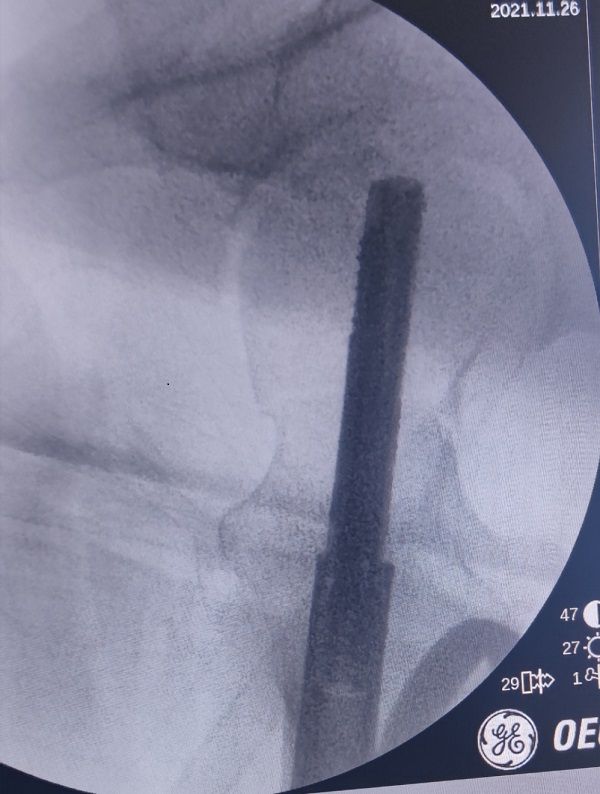

手术中定位:

术后即刻效果:

入院后,创伤骨科王争刚主任医师仔细检查后,向科主任郭永良主任医师汇报。患者骨折移位明显,按以往的固定方法固定之后将来发生骨不连、股骨头坏死几率相当高。为尽可能提升患者今后的生活质量,王争刚主任医师团队经过反复讨论,查阅文献,积极和患者及家属沟通,告知该类骨折的特点及预后,在取得患者及家属同意后,决定对患者实施FNS内固定术。手术由王争刚团队的吴超副主任医师主刀,在骨科专用牵引复位床的辅助下行FNS微创内固定。手术完全闭合复位,对骨折断端的血液循环再无损伤,内固定装置微创植入,患者创伤小,骨折及内固定装置稳定性好,患者正在康复中,目前恢复良好,相信患者将获得一个满意的疗效。